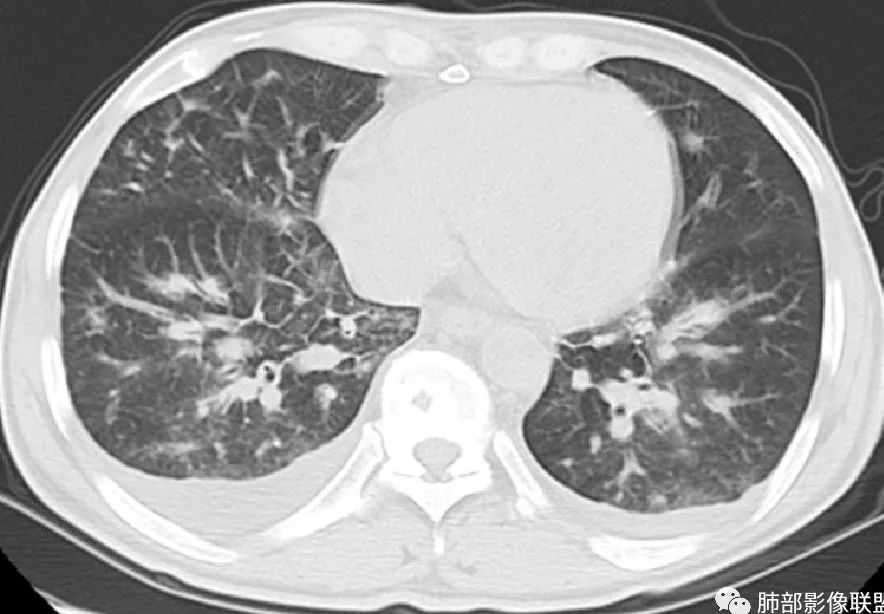

周一晚读病例:男性45岁,发热、纳差,全身散在暗紫色皮疹,结合CD4,符合HIV;肺部影像表现:两肺散在实性结节及磨玻璃密度影,实性结节伴晕征,部分沿支气管血管束分布,支气管血管束增粗,以两肺下叶为著,类似火焰征,双侧胸腔少量积液;首先考虑卡波西肉瘤,鉴别淋巴瘤增值性病变,淋巴瘤样肉芽肿/淋巴瘤,最后挂上马尔尼菲青霉菌病。

两肺弥漫性性结节状、小片状及片状带晕的病灶,煎蛋征、点晕征,主要分布两肺中下叶,病灶周围小叶间隔增厚呈网格状影,部分病灶累及胸膜,伴两侧胸膜增厚。

2.本例双肺小叶间隔增厚明显,多发结节影及片状实性密度影,沿血管支气管束分布为主,两侧较为对称,病灶多环以磨玻璃晕,边界不清。

双侧胸腔少量积液。双肺门及纵隔未见明确肿大淋巴结,纵隔结构间隙模糊。

3.有学者将这种具有沿双肺支气管束分布的实性密度片影描述为“火焰征”,认为具有一定特征性,单就影像表现而言,这种影像表现也可以见于其他病损或多种病理改变的叠加。

1.结节型:两肺沿支气管血管束分布的结节影,呈火焰状或星芒状、挂果征,局部周围出血磨玻璃影(肺泡出血或水肿)。

2.支气管血管束增粗型:

肺门周围支气管壁呈“套袖样”改变。

3.肺炎渗出型:

斑片渗出影,部分融合呈“火焰样”,同时有火焰样结节,小叶间隔增厚等表现。

还可以有纵隔及腋下淋巴结增大,胸腔积液等表现。